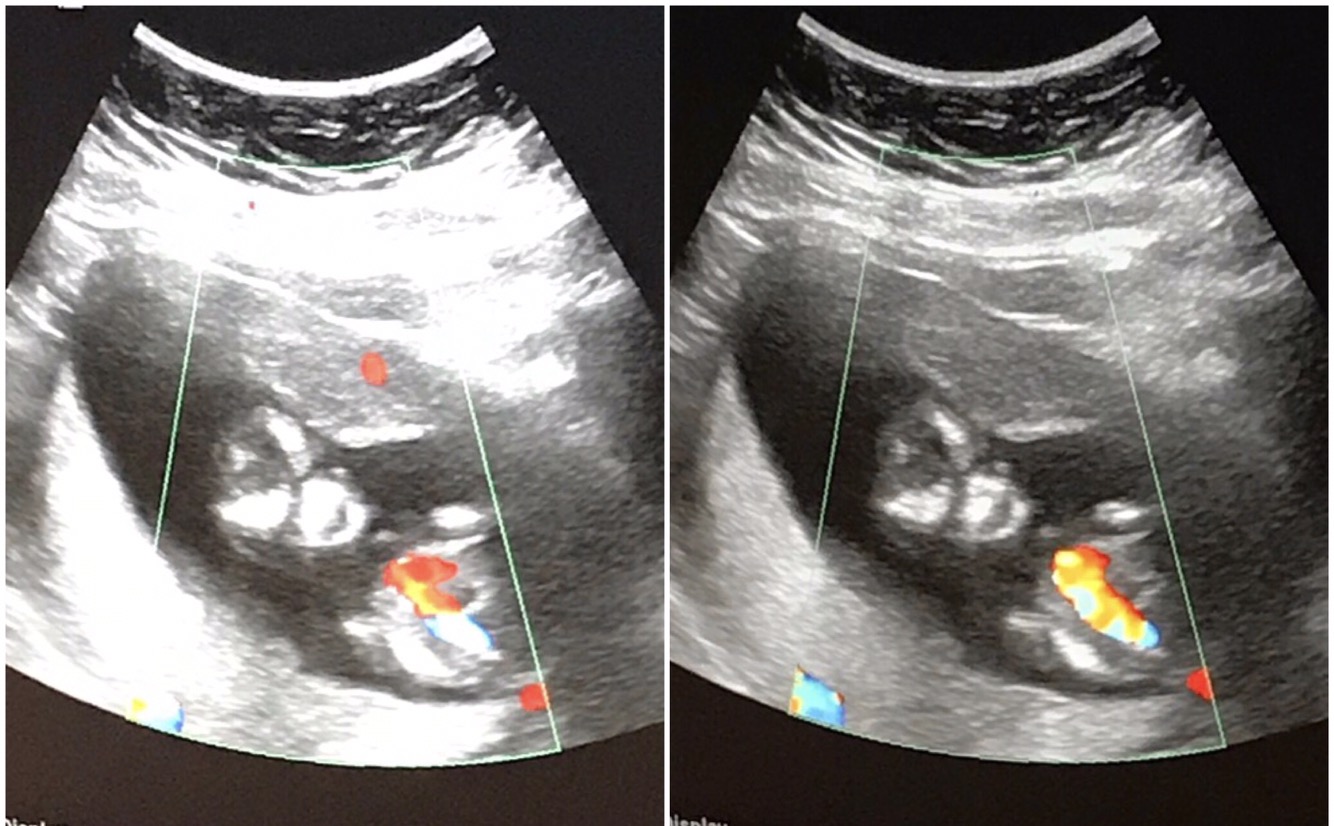

A: Baby has gone through numerous ultrasounds including a very detailed one when I had my NT test and one at every visit with Dr. G except the last one. I haven’t seen baby’s elbows for example, but we’ve seen baby make a fist, we’ve seen baby kick, and we’ve seen, in beautiful rainbow colors and heard the strong heartbeat, and as far as we know baby has all the parts you’d expect in a healthy, growing baby.